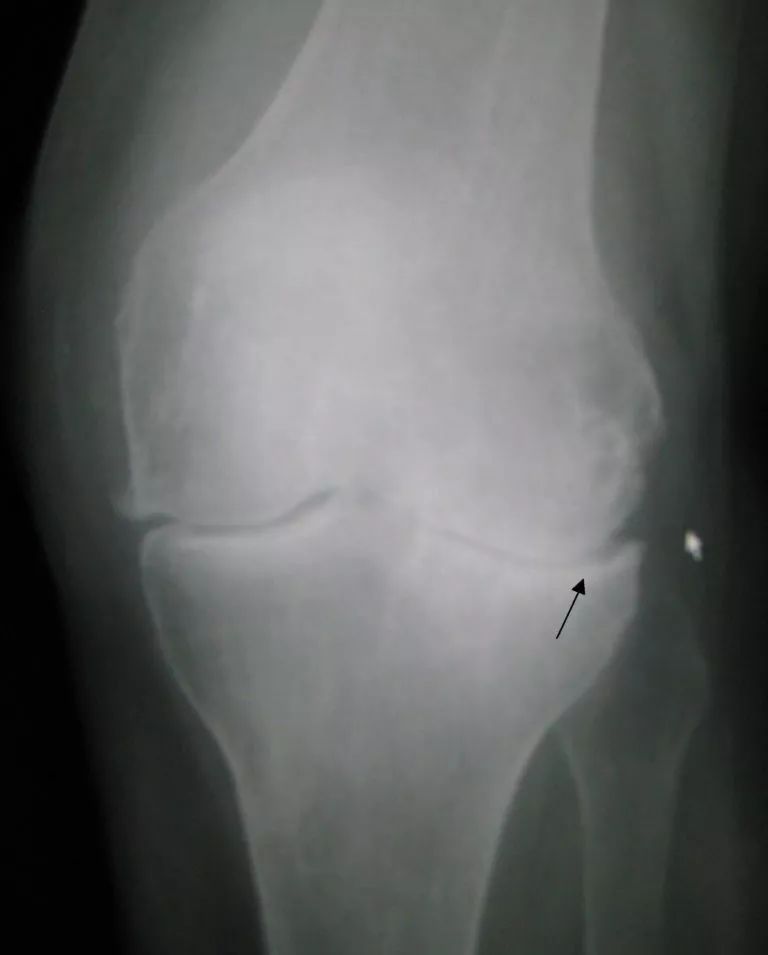

2)创伤后骨关节炎的结构改变更容易发生在膝关节外侧面(Lateral compartment)

患有非创伤性骨关节炎的年龄较大成年人群,常伴有关节结构改变,例如骨刺和关节腔缩窄,最常发生在膝关节内侧面(Medial compartment)。然而,创伤后骨关节炎的结构改变经常均匀的发生在内侧面和外侧面之间(Sward等,2010),更偏向于外侧面。这可能与在膝部创伤时,外侧面更容易损伤有关,且损伤后的关节生物机制随之改变(Stein等,2012)。因此,针对膝关节内侧面的治疗,例如使用膝关节支具减轻关节内侧面应力,或许对创伤后骨关节炎作用不大。

图 创伤后OA更易发生在膝关节外侧面